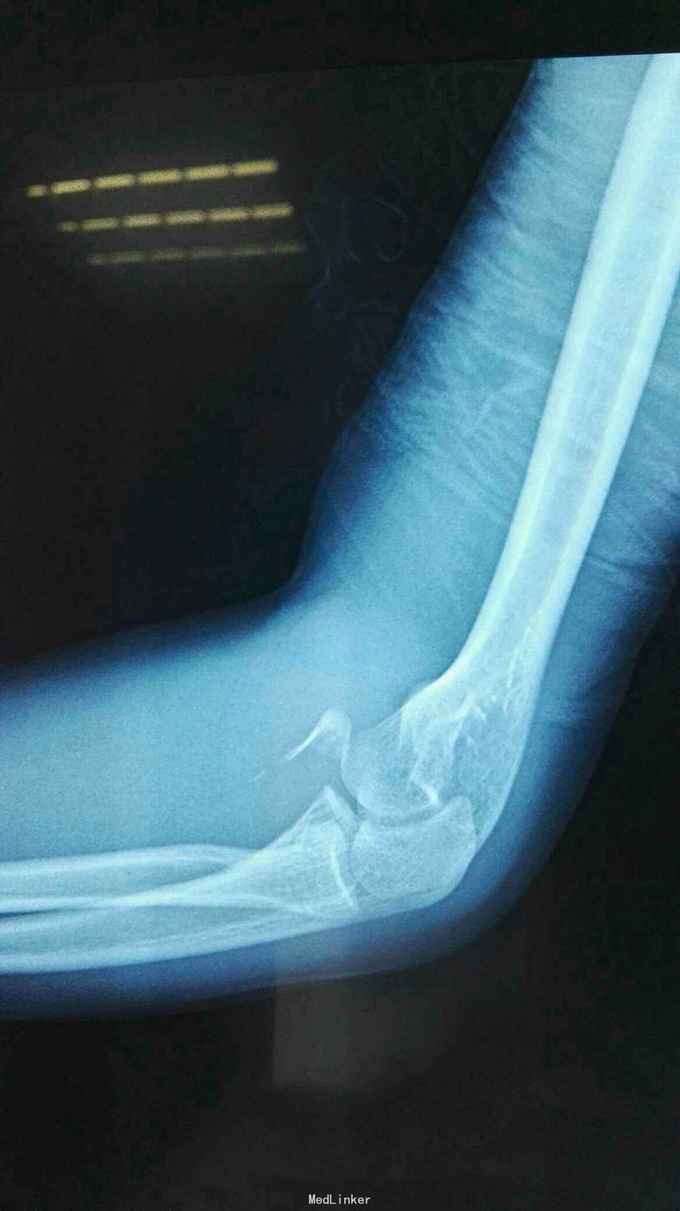

右肘跌伤疼痛伴不能活动1天。 患者,男,14岁,1天前跌倒,感右肘部剧痛,不能活动,急送当地医院拍片示:右肘关节脱位,尺骨冠狀突骨折,右桡骨小头骨折,行手法复位,今来我院就诊。

查体:右肘关节高度肿胀,触痛,活动功能障碍手指末端感觉血运正常。 辅查:x线,CT:右肘关节脱位,右尺骨冠突骨折,右桡骨小头骨折

诊断:右肘恐怖三联症。 治疗:伤后第6天在全麻下行右肘恐怖三联症切开复位内固定术,术中先取肘外侧弧形切口,显露桡骨头,用2枚埋头螺钉固定桡骨头,见右肘外侧副韧带尺侧束断裂,用锚钉固定外侧副韧带。取右肘内侧弧形口,显露冠状突,见冠状突骨折块很小,移位较远,复位,2枚螺钉固定,内侧副韧带前束断裂,修补,术后石膏因定。